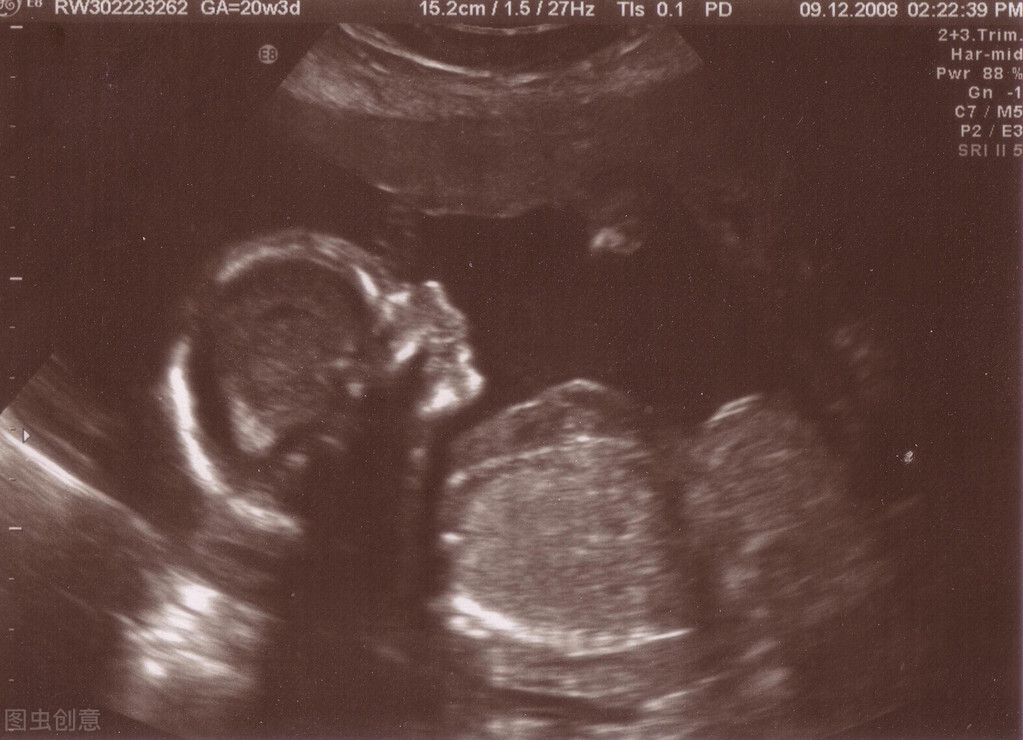

能否受孕除了有正常的生殖功能和健全的组织器官外,还必须要具备发育成熟的卵子和高质量的精子,才能完成受孕过程。广慈医院利用高科技的数码监测系统,对男女双方生殖系统进行全方面的严密监测,根据监测的数据进行综合分析,制定出一整套治疗方案,从而能快速、准确的达到怀孕的目的。

应用数码监控系统可以对卵巢内有无卵泡生长、卵泡是否成熟、卵泡的数量、大小、质量如何、何时排卵、什么时候是受孕的最佳时期等等一系列问题进行仔细观察、全面分析,科学地制定出治疗方案,快速将卵子调整到最佳受孕状态,迎接精子的到来。

子宫腔是孕卵着床发育的场所,子宫腔内环境不良、子宫内膜过厚过薄不适合孕卵的发育,也容易导致流产的发生,应用数码监控系统监测子宫的大小、子宫内膜的厚度、子宫内膜的内分泌变化以及它是否适合孕卵着床发育,何时是孕卵的最佳着床发育期,配合阴式微波和中西药快速将子宫内环境调理到最佳受孕状态,为受精卵着床创造良好的环境。

三、宫内种子